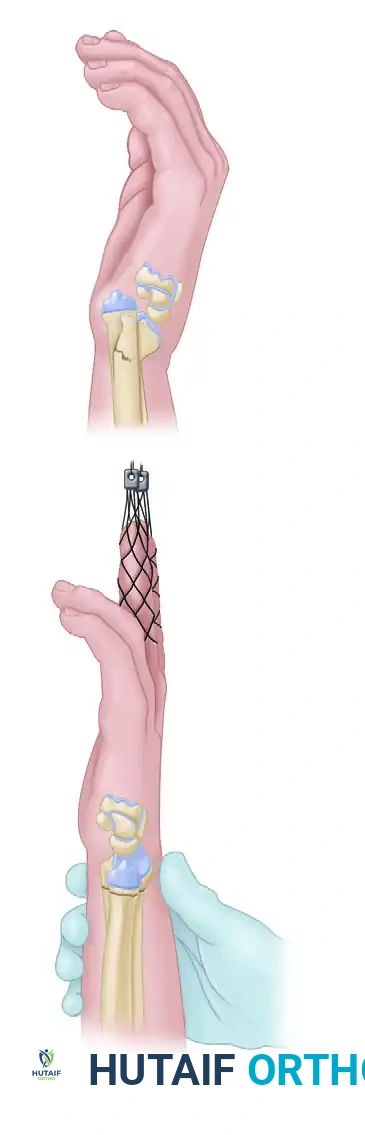

Surgical Technique: Step-by-Step Pinning

1. The Radial Styloid Incision

Make a 1.5-cm longitudinal incision beginning at the tip of the radial styloid and proceeding distally. A percutaneous approach without an incision is strongly discouraged due to the high risk of iatrogenic injury to the superficial radial nerve (SRN).

3. Radial Styloid Pin Placement

Place two 1.6-mm (0.062-in) Kirschner wires in succession. Start at the radial styloid and drive the wires proximally and ulnarly across the fracture site to engage the intact ulnar cortex of the proximal radial shaft.

* These wires can be placed either dorsal or volar to the first extensor compartment, depending on the specific fracture pattern and the patient's anatomical variations.

* Ensure bicortical purchase for maximum stability.

4. Orthogonal Dorsal Pin Placement

To provide multiplanar stability, place a third 1.6-mm K-wire percutaneously at a 90-degree orthogonal angle to the radial styloid pins.

* Start at the dorsal rim of the distal radius, just distal to Lister's tubercle.

* Confirm the correct starting point with fluoroscopy to avoid intra-articular penetration.

* Drive the wire in a proximal and volar direction across the fracture site to engage the volar cortex of the radius proximal to the fracture.

5. Alternative Pin Configurations

Depending on the fracture morphology, alternative or additional pin configurations may be required:

* Dorsal Comminution: A second dorsal pin can be placed into the dorsal rim, or a pin can be utilized as an intrafocal (Kapandji) pin to buttress the dorsal cortex.

* Radial Comminution: If there is marked radial comminution and pre-reduction radial translation, an additional buttress pin can be placed into the radial aspect of the fracture and driven into the proximal ulnar cortex.

* Crossed-Pin Configuration: Pins can be placed from the distal ulnar corner of the radius and passed to engage the intact radial cortex proximally, creating a stable crossed construct.

6. Final Evaluation and Closure

Place additional wires as necessary to secure any remaining unstable fracture fragments. Confirm final reduction and extra-articular pin placement with dynamic fluoroscopy through a full range of motion.

Bend the K-wires and cut them, leaving them superficial to the skin to facilitate easy removal in the clinic. Close the radial styloid incision with interrupted absorbable sutures (e.g., 4-0 Monocryl or Vicryl). Apply sterile dressings and a well-molded sugar-tong splint.